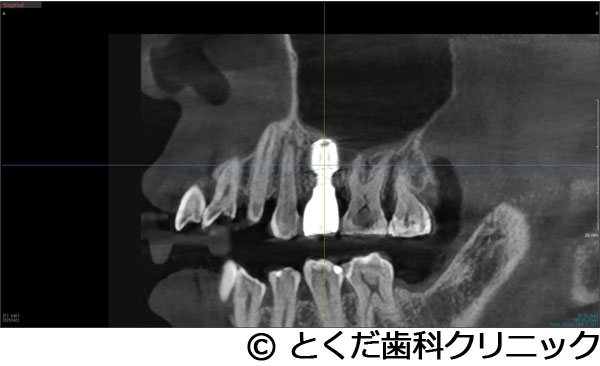

»õ²ÊÍѤΥ³¥ó¥Ó¡¼¥àCT¤Î»£±Æ¥Ç¡¼¥¿¤ä¡¢¸÷³Ø°õ¾Ý¡¢¥·¥ß¥å¥ì¡¼¥·¥ç¥ó¥½¥Õ¥È¤Ê¤É¤ò³èÍѤǤ¤ë¡¢¥³¥ó¥Ô¥å¡¼¥¿¤Ë¤è¤ë¼ê½Ñ¥¬¥¤¥É¥·¥¹¥Æ¥à¤òºÎÍѤ·¤Æ¤¤¤Þ¤¹¡£

ŬÀڤʥ¤¥ó¥×¥é¥ó¥È¤ÎËäÆþ°ÌÃÖ¤ò¥·¥ß¥å¥ì¡¼¥·¥ç¥ó¤¹¤ë¤³¤È¤¬¤Ç¤¡¢¼ê½Ñ»þ¤Ë¤â¥¬¥¤¥É¤¬¤¢¤ë¤³¤È¤Ç¡¢¼ê½Ñ»þ´Ö¤Îû½Ì¤ä¡¢Ä㿯½±¤Ç¤Î¼ê½Ñ¤¬´üÂԤǤ¤Þ¤¹¡£

»õ¼þɤˤè¤ê¡¢±¦Â¦6È֤ξå³Ü¹ü¤¬µÛ¼ý¤·¤Æ¡¢1.5¡Á2mmÄøÅ٤ιü¤·¤«»Ä¤Ã¤Æ¤¤¤Ê¤«¤Ã¤¿¤¿¤á¡¢½¾Íè¤Ê¤éÂ礤ʿ¯½±¤È1ǯ°Ê¾å¤Î¼£ÎÅ´ü´Ö¤¬¤«¤«¤ë¥µ¥¤¥Ê¥¹¥ê¥Õ¥È¤¬É¬ÍפǤ¢¤Ã¤¿¤¬¡¢´µ¼ÔÍͤؤλþ´ÖŪ¡¢ÆùÂÎŪ¡¢¶âÁ¬ÅªÉéô¤¬Â礤¯¤Ê¤ë¤³¤È¤ò¹Íθ¤·¤Æ¡¢º£²ó¤Ï¡¢¥¨¥¯¥¹¥È¥é¥ï¥¤¥É¥·¥ç¡¼¥È¥¤¥ó¥×¥é¥ó¥È¤È¥Ç¥ó¥µ¡¼¥Ð¡¼¤ò»ÈÍѤ·¤¿¥°¥é¥Õ¥È¥ì¥¹¥µ¥¤¥Ê¥¹¥ê¥Õ¥È¤òÁªÂò¤·¤Æ¡¢¤ï¤º¤«¡¢2.5¥õ·î¤Ç¾åÉô¥¸¥ë¥³¥Ë¥¢¤ÎºÇ½ªÊäÄÖʪ¤òÁõÃ夷¤Æ¼£ÎŤò½ª¤¨¤Æ¤¤¤Þ¤¹¡£

¹âÅ٤˵ۼý¤·¤¿¾å³Ü¹ü¤ËÂФ¹¤ë¥¤¥ó¥×¥é¥ó¥È¼£ÎŤǤ¢¤Ã¤¿¤¬¡¢¥°¥é¥Õ¥È¥ì¥¹¥µ¥¤¥Ê¥¹¥ê¥Õ¥È¤ò¹Ô¤¦¤³¤È¤Ç¡¢Ã»»þ´Ö¡Ê11½µ¡Ë¤Ç¼£ÎŤò½ª¤¨¤ë¤³¤È¤¬¤Ç¤¡¢¾å³ÜƶÆâ¤Ë°Ûʪ¤Ç¤¢¤ë¿Í¹©¹ü¤ò»ÈÍѤ·¤Æ¤¤¤Ê¤¤¤¿¤á¤Ë¡¢¥µ¥¤¥Ê¥¹¥ê¥Õ¥È¤Ç¤è¤¯µ¯¤¤ë¹çÊ»¾É¤Î¾å³Üƶ±ê¤òÈò¤±¤ë¤³¤È¤¬¤Ç¤¡¢Ã»»þ´Ö¡¢Ä㿯½±¡¢Ä㥳¥¹¥È¤Ç¼£ÎŤò½ª¤¨¤ë¤³¤È¤¬¤Ç¤¤¿¡£¾å³Ü±¦Â¦6È֤˥¤¥ó¥×¥é¥ó¥È¼£ÎŤǤ¤¿¤³¤È¤Ë¤è¤ê¡¢Òû¹ç¤¬°ÂÄê¡¢»õ¼þɤˤ괵¤·¤Æ¤¤¤ë»õ¤Ø¤ÎÉ԰¤òÍÞ¤¨¤ë¤³¤È¤¬¤Ç¤¤¿¡£

´µ¼ÔÍͤ¬º¸¾å5¤ÎÇÓÇ¿¤ò¼çÁʤËÍ象¡¢¾Ã±ê¸å¤ËÈ´»õ¤ò´õ˾¤·¤¿¤¿¤áÈ´»õ¤ò¹Ô¤¤¤Þ¤·¤¿¡£¤½¤Î¸å¡¢´µ¼ÔÍͤ¬¥¤¥ó¥×¥é¥ó¥È¼£ÎŤò´õ˾¤·¤¿¤¿¤áÈ´»õ¸å¡¢¼þ°ÏÁÈ¿¥¤¬°ÂÄꤹ¤ë¤Î¤òÂԤäƥ¤¥ó¥×¥é¥ó¥È¼ê½Ñ¤ò¹Ô¤Ã¤Æ¤¤¤Þ¤¹¡£ÆâÍÆ¤Ï¡¢¾å³Ü´û¸¹ü¤¬Çö¤¤¤¿¤á¥°¥é¥Õ¥È¥ì¥¹¥µ¥¤¥Ê¥¹¥ê¥Õ¥È¤ÈʹԤ·¤Æ¡¢¹ü¤¬ÂçÉý¤Ë·ç»¤·¤¿Éôʬ¤Ø¤Î¹üÊäŶºÞŶÆþ¤ò¹Ô¤¤1²óË¡¤Ç¼ê½Ñ¤ò´°Î»¤·¡¢9½µ¸å¤Ë¸÷³Ø°õ¾Ý¤Ç°õ¾Ý¤ò¹Ô¤¤¡¢¥¸¥ë¥³¥Ë¥¢¤ÎºÇ½ªÊäÄÖʪ¤ò11½µ¤ÇÁõÃ夷¤Æ¼£ÎŤò´°Î»¤·¤Æ¤¤¤Þ¤¹¡£

ÂçÉý¤Ê¹ü·ç»¤¬¤¢¤Ã¤¿¤¬¡¢¥°¥é¥Õ¥È¥ì¥¹¥µ¥¤¥Ê¥¹¥ê¥Õ¥È¤È¹ü·ç»Éô¤Ë¿Í¹©¹ü¤òÊäŶ¤·¤Æ¡¢¤ï¤º¤«2¥õ·îȾ¤Ç¼£ÎŤò´°Î»¤¹¤ë¤³¤È¤¬¤Ç¤¤¿¡Ê²¾¤Ë¡¢GBR¤äÄ̾ï¤Î¥µ¥¤¥Ê¥¹¥ê¥Õ¥È¤ò¹Ô¤¤¼£ÎŤò¹Ô¤Ã¤Æ¤¤¤¿¤é¡¢ºÇÄã¤Ç¤â1ǯ¤Ï¤«¤«¤ë¥±¡¼¥¹¤Ç¤¹¡Ë¡£Ä㿯½±¤Ç¡¢Ã»»þ´Ö¤Ç¡¢¼£ÎŤò½ª¤¨¤ë¤³¤È¤¬¤Ç¤¡¢¤Þ¤¿¡¢¿³ÈþÀ¡¦µ¡Ç½À¤Î²óÉü¤â¹Ô¤¦¤³¤È¤¬¤Ç¤¤¿¡£

´µ¼ÔÍͤϺ¸¾å¤ÎưÍɤ¬º¸¾å56¤ÎÈ´»õ¤ò´õ˾¡£¤½¤Î¸å¡¢¥¤¥ó¥×¥é¥ó¥È¼£ÎŤò´õ˾¤·¤¿¤¿¤áº¸¾å4¤Ë´Ø¤·¤Æ¤ÏÈ´»õ¨»þËäÆþ¡£º¸¾å6¤Ë´Ø¤·¤Æ¤Ï¡¢´û¸¹ü1¡Á2mm¤Ç¥¤¥ó¥×¥é¥ó¥È¼£ÎŤ¬¸·¤·¤¤¾õÂ֤Ǥ¢¤Ã¤¿¤¬¡¢¥°¥é¥Õ¥È¥ì¥¹¥µ¥¤¥Ê¥¹¥ê¥Õ¥È¤Ç¥¤¥ó¥×¥é¥ó¥ÈËäÆþ¤ò¹Ô¤¤¤Þ¤·¤¿¡£¤½¤Î¸å¡¢2¥õ·îȾ¸å¡¢ÂçÉý¤Ë¹ü¤¬·ç»¤·¤Æ¤¤¤ë²¼³Ü56¤ËÂФ·¤Æ¥·¥ç¡¼¥È¥¤¥ó¥×¥é¥ó¥È¤ò»ÈÍѤ·¤Æ¡¢²¼³Ü¿À·Ð¤Î»½ý¤òÈò¤±¤Æ¥¤¥ó¥×¥é¥ó¥ÈËäÆþ¤Î¼ê½Ñ¤ò½ª¤¨¤Æ¤¤¤Þ¤¹¡£¤½¤Î¸å2¥õ·î¸å¤Ë¸÷³Ø°õ¾Ý¤Ç°õ¾Ý¤ò¹Ô¤¤¡¢º¸¾å456¤Ï3¥æ¥Ë¥Ã¥È¤Î¥¸¥ë¥³¥Ë¥¢¥Ö¥ê¥Ã¥¸¤òÁõÃå¡£²¼º¸56¤Ë´Ø¤·¤Æ¤Ï¹ü·ç»¤¬Â礤¤¤¿¤á¡¢»õ´§Ä¹¤¬¤À¤¤¤ÖŤ¯¤Ê¤ë¤¿¤á¡¢¥¸¥ë¥³¥Ë¥¢¤ÎÏ¢·ë´§¤òÁõÃ夷¤Æ¼£ÎŤò½ª¤¨¤Æ¤¤¤Þ¤¹¡£

¾å³Ü6¤Ë´Ø¤·¤Æ¤Ï´û¸¹ü¤¬¾¯¤Ê¤¯¡¢¸·¤·¤¤¼£ÎŤǤϤ¢¤ê¤Þ¤·¤¿¤¬¡¢5¥õ·î¤Ç¼£ÎŤò½ª¤¨¡¢´µ¼ÔÍͤοÈÂÎŪ¡¢»þ´ÖŪ¡¢ÈñÍÑŪÉéô¤òºÇ¾®¸Â¤ËÍÞ¤¨¤ë¤³¤È¤¬¤Ç¤¤¿¤È¹Í¤¨¤Þ¤¹¡ÊÄ̾ï¤À¤È¼£ÎŤ¬ÉÔ²Äǽ¤È¸À¤ï¤ì¤ë¤³¤È¤¬Â¿¤¤¥±¡¼¥¹¤À¤È¹Í¤¨¤Þ¤¹¡£¤Ç¤¤¿¾ì¹ç¤â¡¢½¾Íè¤Î¥µ¥¤¥Ê¥¹¥ê¥Õ¥È¤ò¹Ô¤¤¡¢1ǯ°Ê¾å¤«1Ç¯ÄøÅ٤μ£ÎÅ´ü´Ö¤¬¤«¤«¤ë¤«¡¢»þ´ÖŪ¤ä¿ÈÂÎŪ¤Ë¤â¡¢¤Þ¤¿¡¢ÈñÍÑÌ̤ˤª¤¤¤Æ¤â¡¢´µ¼ÔÍͤËÉéô¤ò¤«¤±¤ë¥±¡¼¥¹¤À¤È¹Í¤¨¤Þ¤¹¡Ë¡£¤Þ¤¿¡¢²¼³Ü¤Ï¹ü·ç»¤¬Â礤¯¡¢²¼»õÁå´É¤Ø¤Î±Æ¶Á¤¬¹Í¤¨¤é¤ì¤ë¥ê¥¹¥¯¤¬¹Í¤¨¤é¤ì¤ë¥±¡¼¥¹¤Ç¤·¤¿¤¬¡¢¥·¥ç¡¼¥È¥¤¥ó¥×¥é¥ó¥È¤ò»ÈÍѤ¹¤ë¤³¤È¤Ç°ÂÁ´¤Ë¼£ÎŤò½ª¤¨¤ë¤³¤È¤¬¤Ç¤¤Þ¤·¤¿¡£